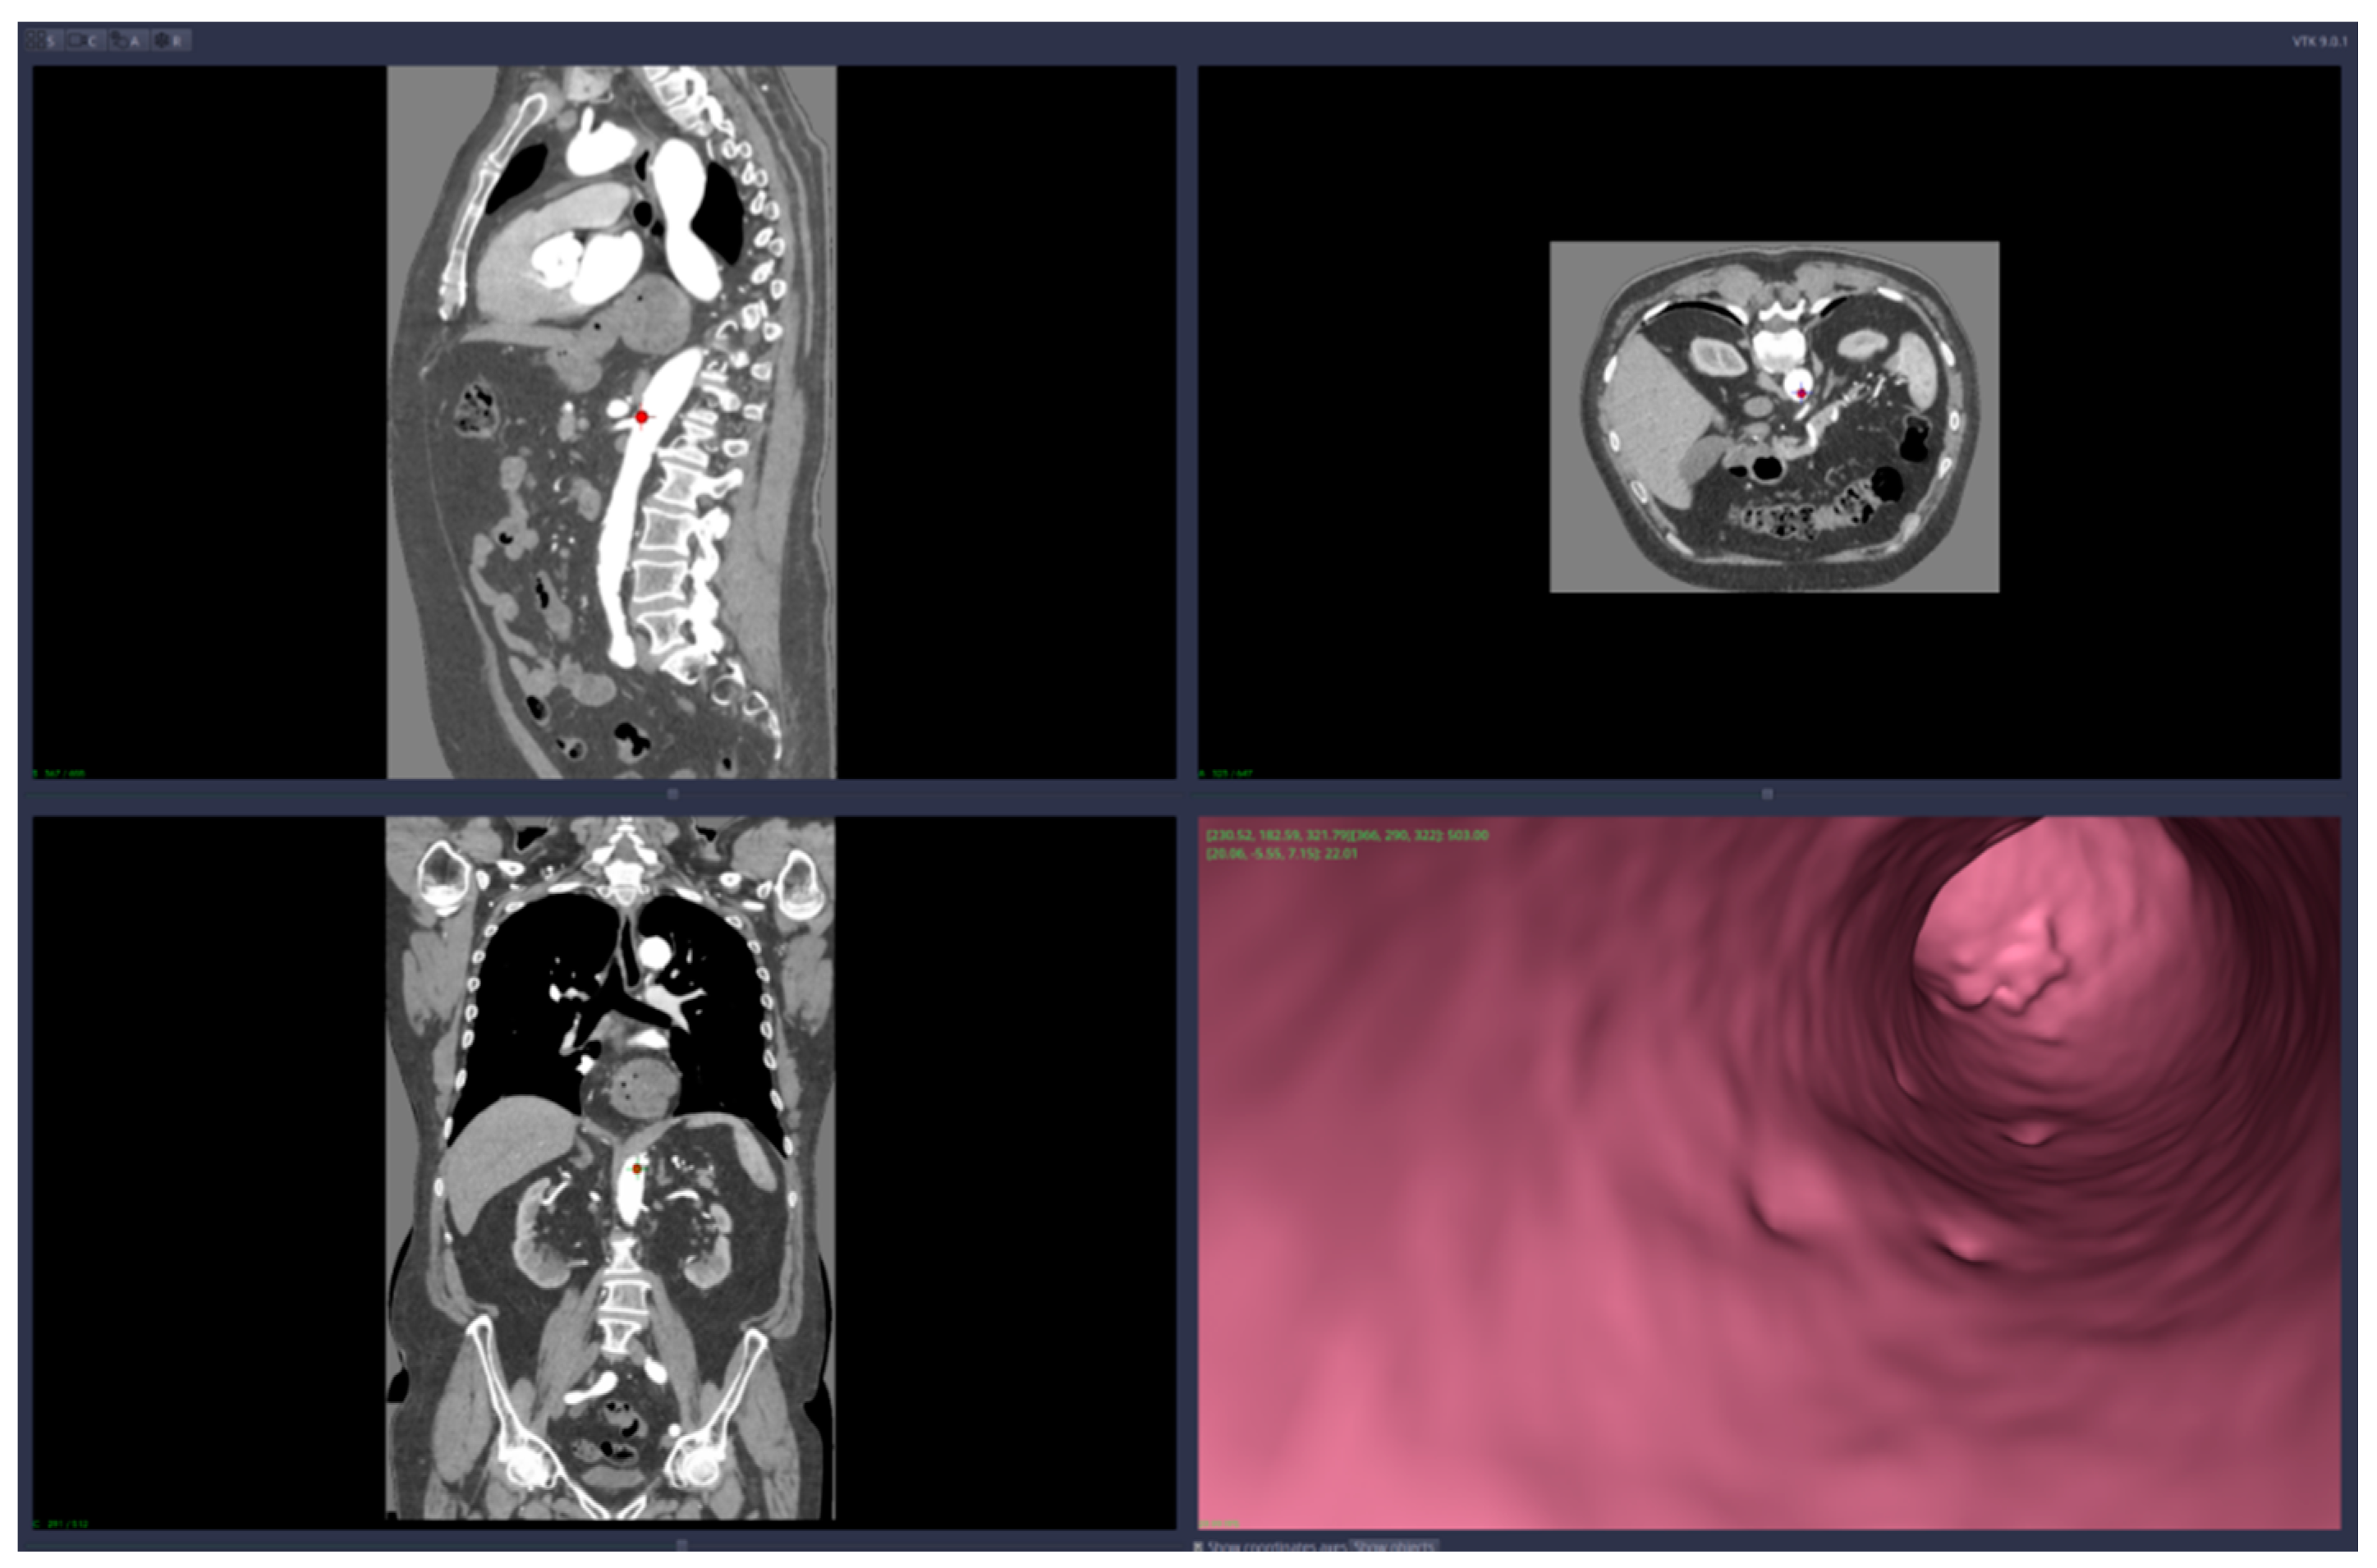

• Virtual angiography—virtual 3D navigation through the mesenteric artery and aneurysm zone (see Figure 3, Figure 4, Figure 5, Figure 6 and Figure 7)

Figure 4. Virtual angiography—inside the mesenteric artery aneurysm (direction is opposite to the blood flow).